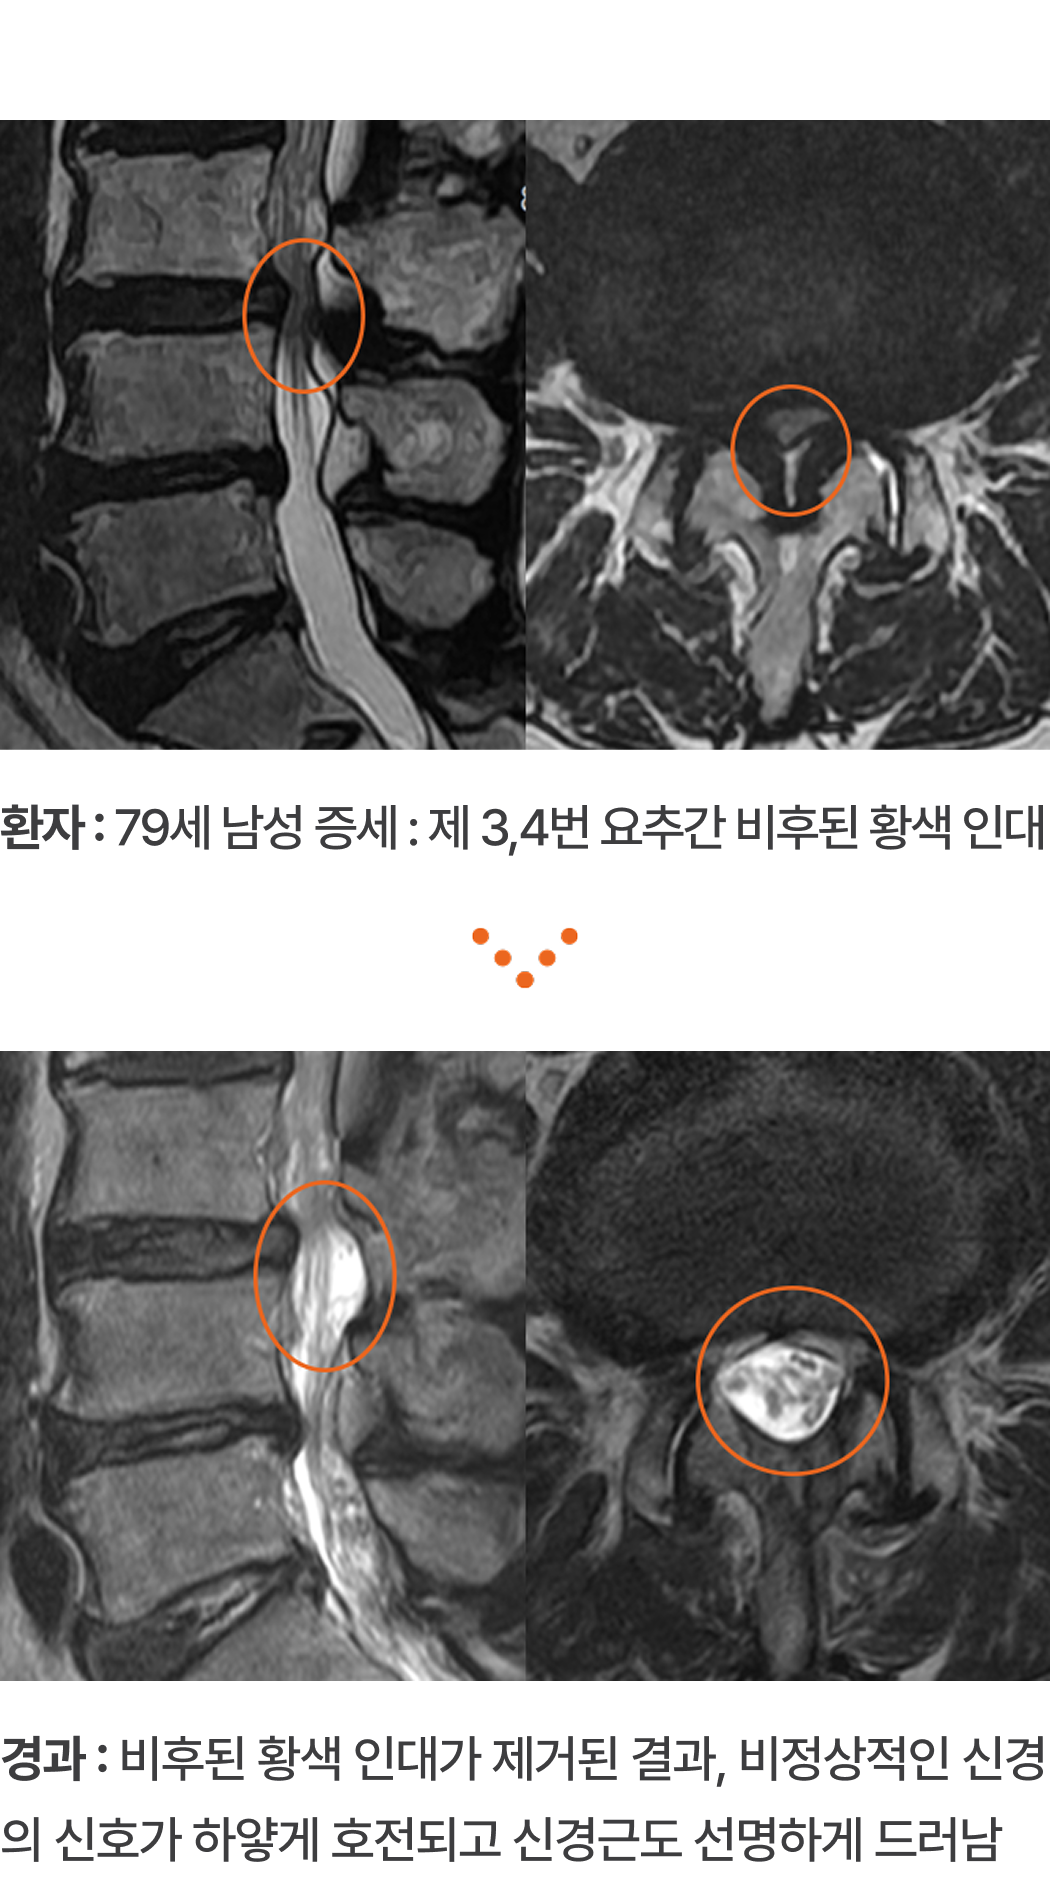

환자 : 79세 남성 증세 : 제 3,4번 요추간 비후된 황색 인대

경과 : 비후된 황색 인대가 제거된 결과, 비정상적인 신경의 신호가 하얗게 호전되고 신경근도 선명하게 드러남